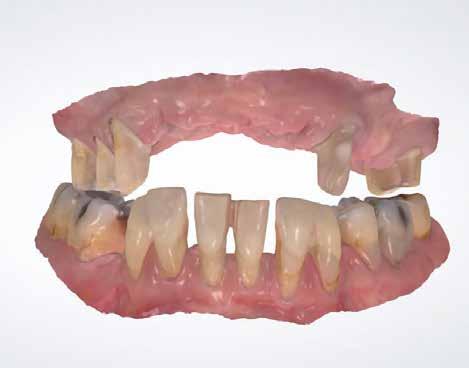

1–2. képek: Kiindulási helyzet.

3. kép: Új teleszkópos fogpótlás az 16, 15, 13, 23 és 27 fogakra.

Teleszkópos munka, élő eset bemutatásával ismertetem, mi az, ami már lehetséges. A munkaasztal-szkenneren kívül bevetésre került a digitális munkafolyamatok során egy intraorális szkenner (IOS) is. A 3D nyomtatású testek gyártása a laboratóriumban LCD- és DLP nyomtatókkal történt. A fémes komponenseket szelektív lézerolvasztásos (SLM) technológiával készíttettük.

Kiindulási helyzet

A páciens látlelete a következő:

• krónikus általános parodontitis

• a 24-től terjedő parodontális fekély

• hatástalan kapcsos felső fogpótlás (1-2. képek)

Terápia

A kezelőorvos (dr. Werner Knapp, Würzburg) ennek alapján a következő terápiát javasolta:

• a 24-es fog extrakciója, illetve az 12 és 22 fogak extrakciója előrehaladott szövetveszteség okán

• szisztematikus parodontitis-terápia

• új, teleszkóp-elhorgonyzású felső fogpótlás az 16, 15, 13, 23 és 27 fogak felhasználásával (3. kép)